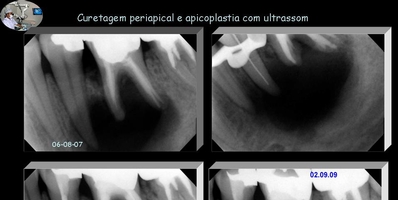

Curetagem Periapical

O que se sabe é que todo processo periapical crônico é acompanhado por uma erosão apical do cemento e dentina, estabelecendo aí nichos microbianos que necessitam ser eliminados. Pois não é suficiente a remoção apenas do peça patológica, mas sim, a remoção também destes nichos impregnados no ápice dental.

A curetagem apical é um procedimento que deve ser realizado com muita precisão. Tem como objetivo remover o processo patológico como também a sua causa. A dificuldade é estabeler que a causa está na porção externa apical. Em que, uma curetagem com apicoplastia, removendo cemento erosado e contaminado por nichos microbianos, promoveria a cura.